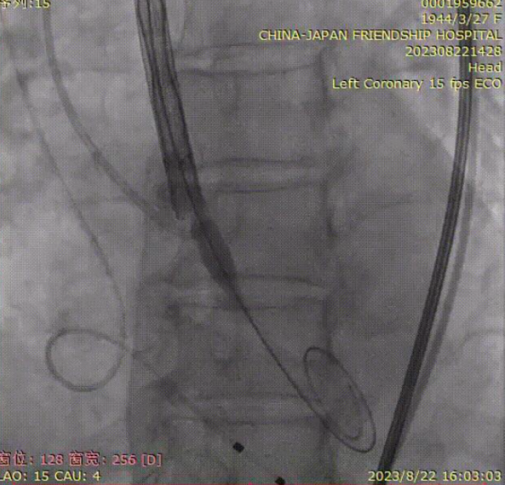

主动脉弓造影,观察头臂干、颈总动脉和左锁骨下动脉形态;

脑保护输送系统置入;

导丝跨瓣;

猪尾导管交换预塑形导丝;